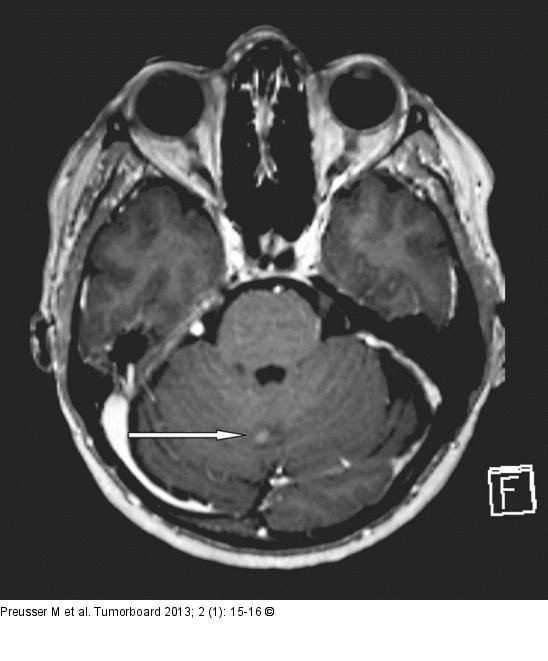

Abbildung 2: Meningeosis carcinomatosa Axiale T1-gewichtete Sequenz des Gehirnschädels. Noduläre leptomeningeale Kontrastmittel- aufnehmende Läsion zerebellär rechts paramedian, hinweisend auf eine beginnende Meningeosis carcinomatosa |

Axiale T1-gewichtete Sequenz des Gehirnschädels. Noduläre leptomeningeale Kontrastmittel- aufnehmende Läsion zerebellär rechts paramedian, hinweisend auf eine beginnende Meningeosis carcinomatosa |